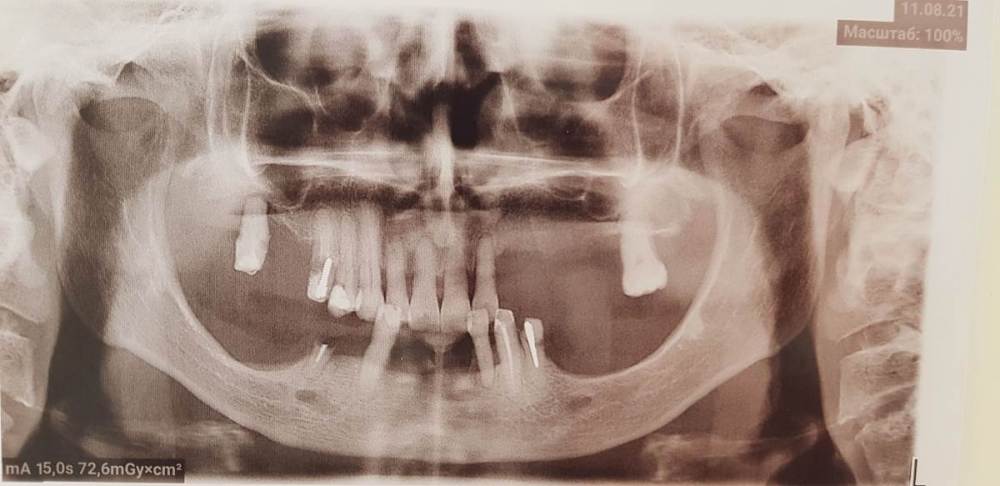

Fatal Опубликовано 6 сентября, 2021 Поделиться Опубликовано 6 сентября, 2021 (изменено) Доброго времени суток коллеги. Есть один клинический случай, где я планирую сделать все на 4, возможно с немедленной нагрузкой. Столкнулся с тем, что foramen mentale четко видно, но ''веточка'' от него выходит еще более медиально особенно в 4 квадранте (фото прилагаю) и тогда не получается поставить имплант в области 44 зуба под углом, что б шахта выходила более дистально для меньшего рычага. (планировалось закончить пятыми зубами или 6ки размоделировать как премоляры). Атрофия значительная в жевательном отделе, костные пластики не планируются. Импланты на фото расставлены примерно, для понимания картины. Вопрос: как ставить имплант в области 44 зуба, если '' веточка'' ментале выходит еще более медиально, также с зоной безопасности в 2 мм? (тогда я упрусь в имплант в области 41-42) -- 4 фото, обведено красным Изменено 6 сентября, 2021 пользователем Fatal Ссылка на комментарий